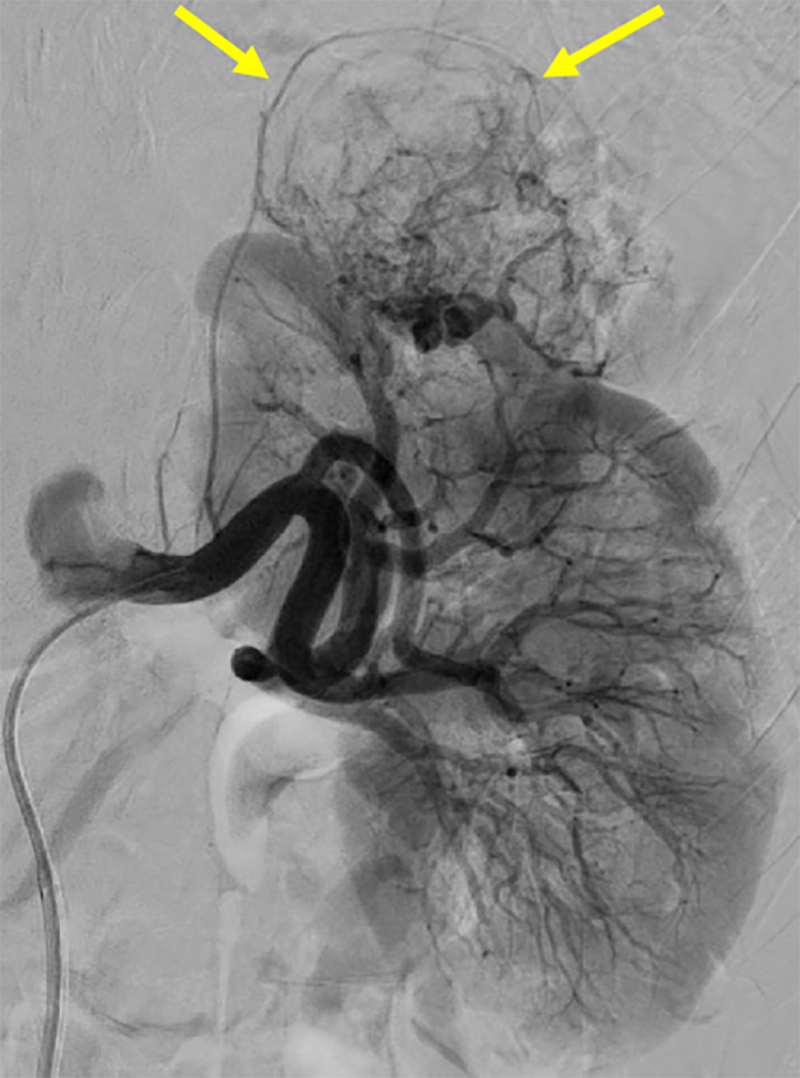

本症例では術前の造影CTから左腎動脈上極枝のほか、左腎動脈本幹から分岐する左上腎被膜動脈が栄養血管として同定され、この画像情報を参考にして塞栓術が施行された。術中の血管造影においても左上腎被膜動脈が腫瘍を栄養する血管として確認され、術前の造影CT所見の通りであった。

治療計画の観点からも、造影CTは重要な役割を果たす。予防的腎動脈塞栓術(TAE)を計画する際、造影CTによる術前の血管マッピングが有用である。腎動脈の走行や異所性腎動脈の有無、腫瘍栄養血管の同定など、詳細な血管解剖の把握が可能となる。この術前評価により、選択的塞栓術の成功率を向上させるだけでなく、正常腎実質への影響を最小限に抑え、腎機能を最大限温存することができる。したがって、ヨード造影剤アレルギーや腎機能低下などでヨード造影剤の使用が禁忌となる場合を除いて、治療前に造影CTを施行することが推奨される。